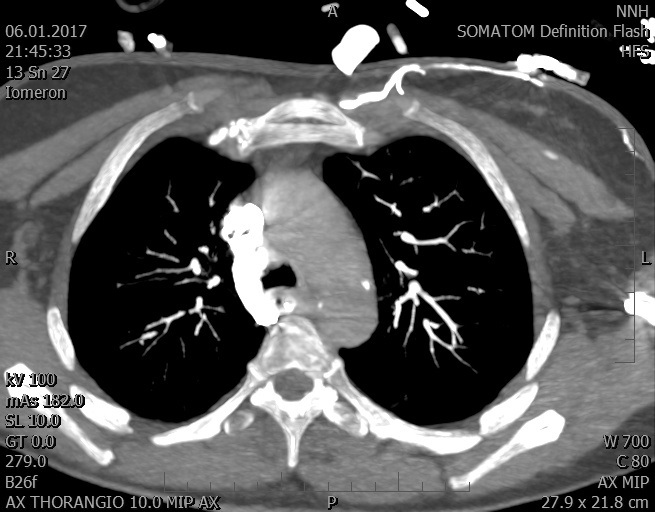

Video 1 - Akutní koronarografie prokázala normální nález na věnčitých tepnách s výjimkou suspekce na lehký spasmus na pravé koronární tepně.Echokardiograficky byla zjištěna těžká dysfunkce dilatované levé komory s nezvětšenou pravou komorou (video 2).

Video 2 - Echokardiograficky byla zjištěna těžká dysfunkce dilatační levé komory s nezvětšenou pravou komorou.Pro nejasnou příčinu zástavy jsme provedli i vyšetření výpočetní tomografií (CT), které vyloučilo plicní embolizaci (série 1 - soubory na konci článku). V den přijetí při přetrvávající oběhové nestabilitě byla nemocná opakovaně defibrilována pro fibrilaci komor se stabilizací rytmu po podání amiodaronu a mesocainu. Dle hemodynamických měření se jednalo o těžký kombinovaný šok. Vstupní laboratorní vyšetření bylo bez větších pozoruhodností. Posléze jsme doplnili anamnézu od příbuzných a zjistili, že pacientka užila do dvou hodin před srdeční zástavou první tabletu amoxicilinu na lehký respirační infekt. Při nevýtěžnosti vstupních vyšetření a nových anamnestických informacích jsme doplnili 14 hodin po kolapsu vyšetření koncentrace tryptázy v séru, která byla extrémně zvýšena (tabulka 2), což nás vedlo k podezření na anafylaxi.